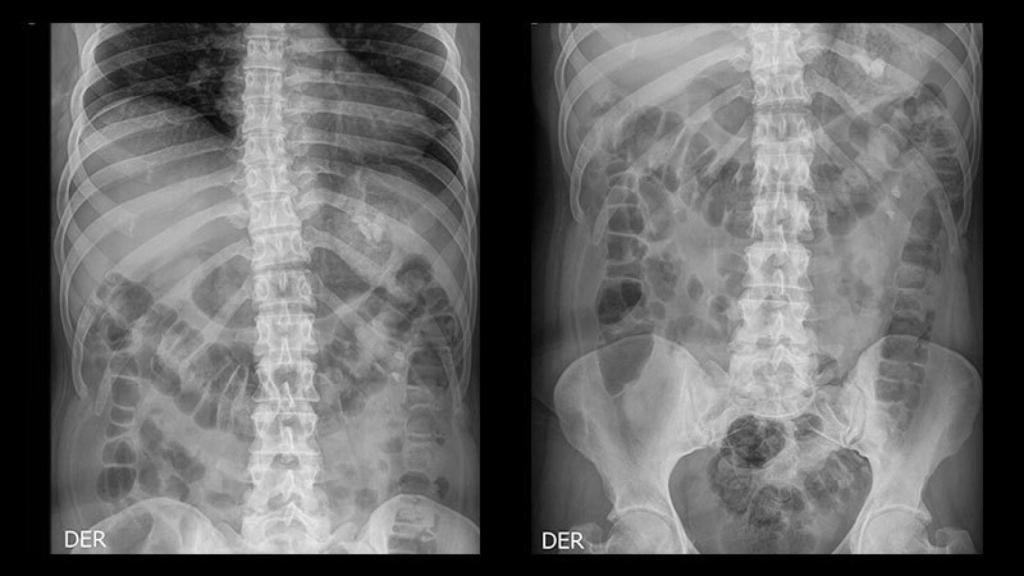

Una radiografía renal y vesical.

El problema es que dicha masa no era un tumor. Se trataba de uno de los riñones de la paciente, sano y completamente funcional. Es lo que se denomina riñón pélvico o riñón ectópico. Se trata de un riñón sano y normal, pero que no ha ascendido correctamente durante el desarrollo fetal y finalmente se localiza en una zona inferior a la normal.

Además, en este caso, y como suele ser habitual en cualquier cirugía de columna vertebral, la paciente fue sometida hasta a dos pruebas de resonancia magnética, la mejor prueba de imagen para estudiar esta zona del organismo humano. Y en ambas pruebas se visualizó el riñón pélvico, según consta en la demanda interpuesta por la paciente.

Según el texto, Pacheco se reunió con el cirujano por primera vez antes de la cirugía de columna vertebral, momento en el cual el médico le explicó que él prepararía la zona quirúrgica pero otros dos compañeros realizarían el procedimiento de fusión vertebral. Sin embargo, y siempre según la demanda, el cirujano "se desvió de los estándares de atención médica" y "no realizó revisiones radiológicas" ni "informó a la paciente" previamente a la extracción de la masa que se confundió con un tumor maligno.